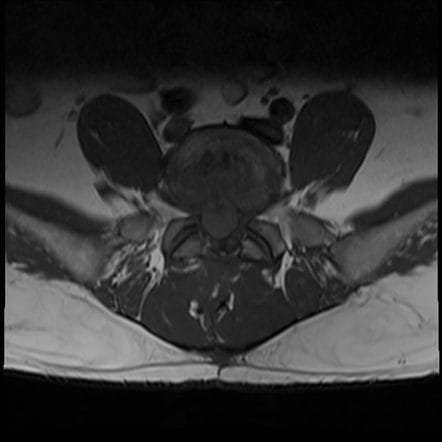

El abombamiento discal es una deformación del disco intervertebral que se desplaza o se rompe parcialmente creando un abultamiento que sobresale hacia el canal espinal. Aunque puede presentarse en cualquier parte de la columna, es más frecuente en la columna lumbar, especialmente en los niveles L4-L5, debido a la gran carga mecánica que soporta esta zona.

¿Qué síntomas causa el abombamiento discal L4-L5?

La protrusión discal de L4-L5 puede ser totalmente asintomático o, por el contrario, causar síntomas muy similares a los de una hernia discal, aunque los síntomas pueden variar según la ubicación y la magnitud de la protrusión. No obstante, los síntomas más habituales son: